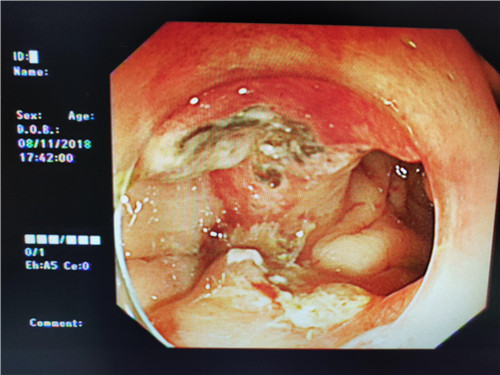

在检查过程中,当曹鹏主治医师将内镜进至吻合口狭窄处时,却偶然发现狭窄部位旁边还有一小小入口,探镜而入,发现这条小小隧道与狭窄部一同通向肠腔,中间相隔了一条不宽不窄的“桥梁”,把本来通畅的“大路”隔成了两条幽径小道,因此患者排便才会堵塞不通。经过反复观察,仔细斟酌后曹鹏医生萌生了,把“桥梁”拆掉,使“曲径小路”变“宽敞大道”的想法。因为这时如果按原计划行肠镜下吻合口扩张术已经没有太大的意义,但肠道薄弱容易造成穿孔,“桥梁”处是否有大的血管,存在出血、穿孔的风险等等,这些都需要与主管医生进一步探讨。随即他与普通外科史和平主任,消化内镜室王莹主任会诊后决定实施“粘膜桥离断术”(ESD内镜下粘膜剥离术)。将术中风险及意外向患者及家属充分告知后,征得患者家属同意签字,随后便开始施行手术。在史主任、王主任、李侠护士长的支持保驾护航之下,曹鹏医生以精湛的医疗技术,与护士的默契配合,顺利完成了手术,术中无出血、穿孔,眼前显示器屏幕上出现了预期中的“宽敞大道”,手术成功了!大家原本绷紧的面容出现了笑容。患者从此以后不会再有排便不畅的痛苦了,患者唐某及家属,欣喜及感激之情溢于言表,医生们再一次为他解决了一件大事情,患者术后恢复良好。